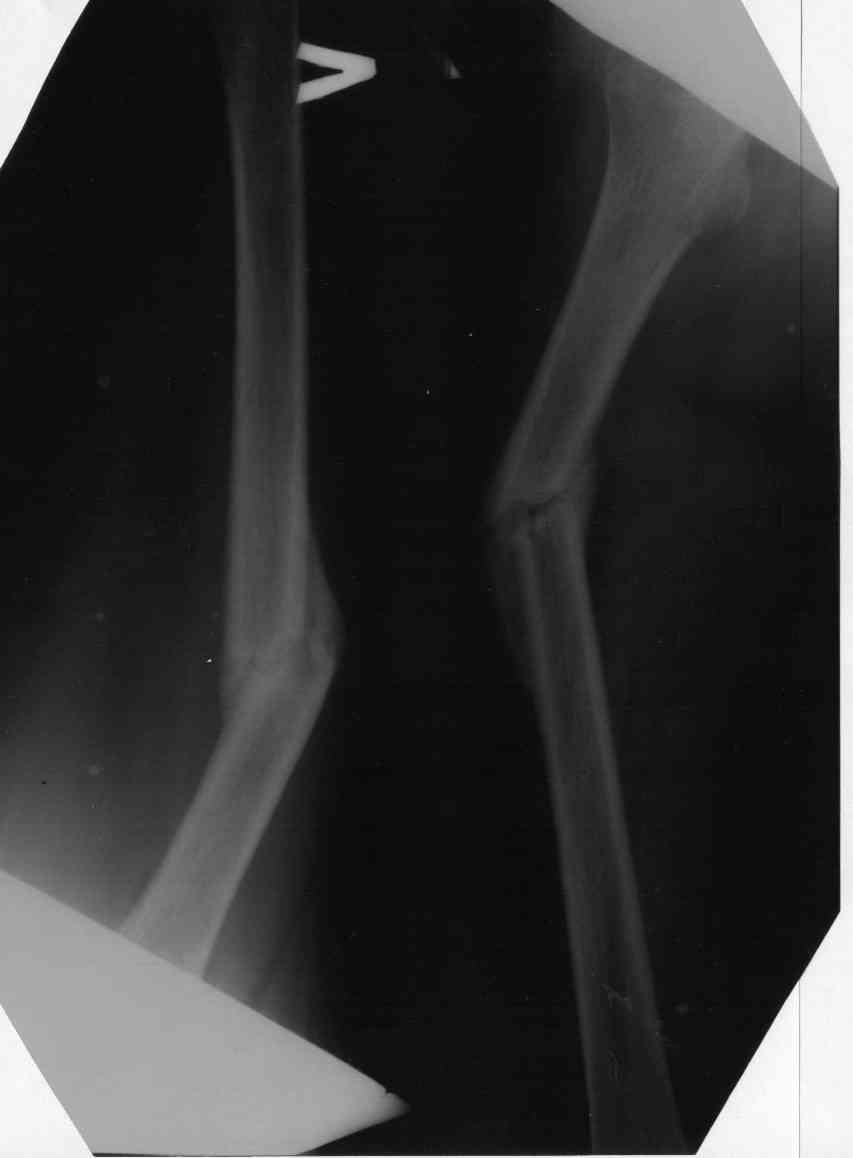

7 сентября 2006 дочь попала в аварию2 месяца на скелктном вытяжении привели к выравниванию с небольшим искажением(3-5 градусов), потом (церкуляр),и повторное смешение...ренген в гипсе- угол 45 градусовбез гипса - развернутый -150 врач категорически против операции(Симферополь, Крым), говорят лежать еще год, в то время как видя ренгены в Харьковском институте ортопедии нам сказали что операция необходима. Каково будет ваше мнение.При каком градусе угла можно становиться на ногу.

Вообще, деформация очень выраженная.

Вытяжение при переломах бедра из-за таких результатов давно вышло из практики уже не только в развитых странах. План "лежать еще год" не решит имеющуюся проблему, а породит новые, поэтому он, мягко говоря, малоприемлемый.

Если есть проблемы с движениями в коленном суставе, то начать с разработки, а после восстановления - исправлять ось. Можно аппаратом, можно заштифтовать закрыто.